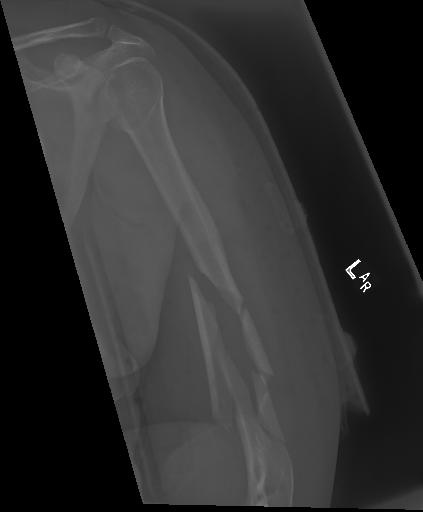

Bone 이미지 데이터 350장 중 Fracture 이미지 50장, Implant 이미지 50장, Bone 이미지 50장을 선별했다.

이렇게 균형을 맞춘 데이터를 train에 100장, val에 40장, test용 10장으로 나눴다.

train과 val은 라벨링을 해야한다. 어제 라벨링을 했었지만, Fracture는 좀 넓게 잡고, Implant는 최대한 여러개로 쪼개는 느낌으로 라벨링을 다시했다.